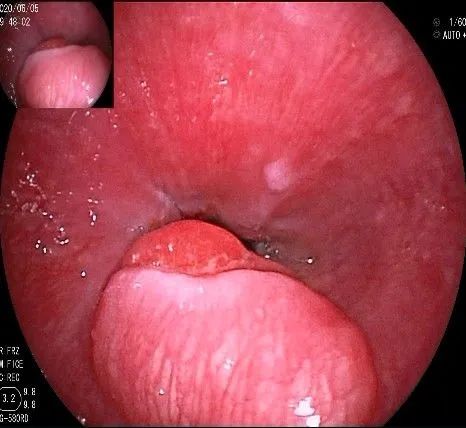

我们的思路:病变长径约2.0cm,位置活动,倒镜后先在胃底侧粘膜下注射,使病变向食管腔方向抬举,然后再在食管腔内做粘膜下注射切开,以获得一个好的术野,果然,注射后粘膜抬举明显,瘤体被挤向口侧。

正镜观察,瘤体就在贲门部齿状线的下方。